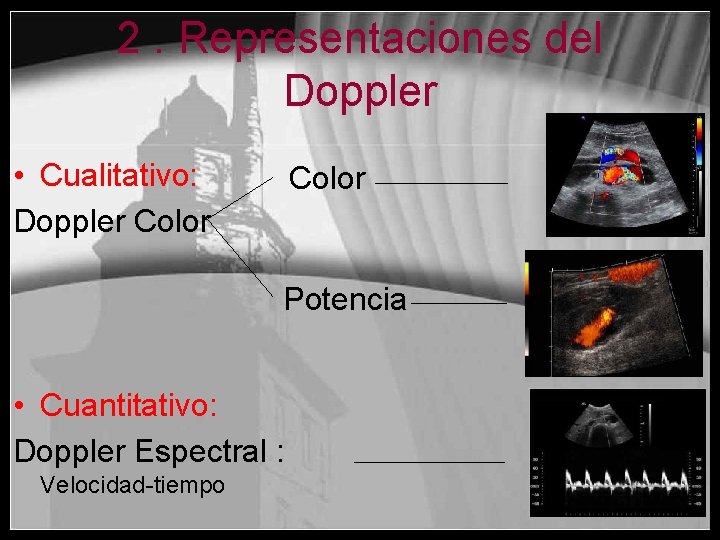

2. Representaciones del Doppler • Cualitativo: Doppler Color Potencia • Cuantitativo: Doppler Espectral : Velocidad-tiempo